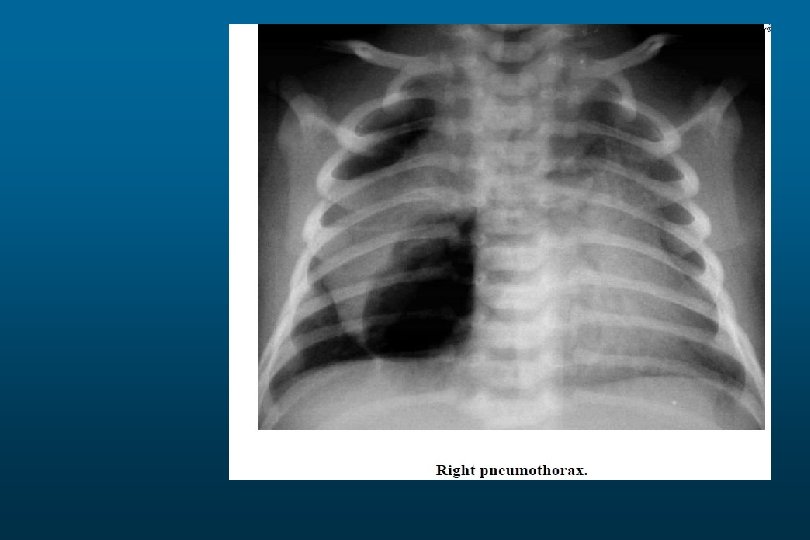

Pneumothorax

Pneumothorax.